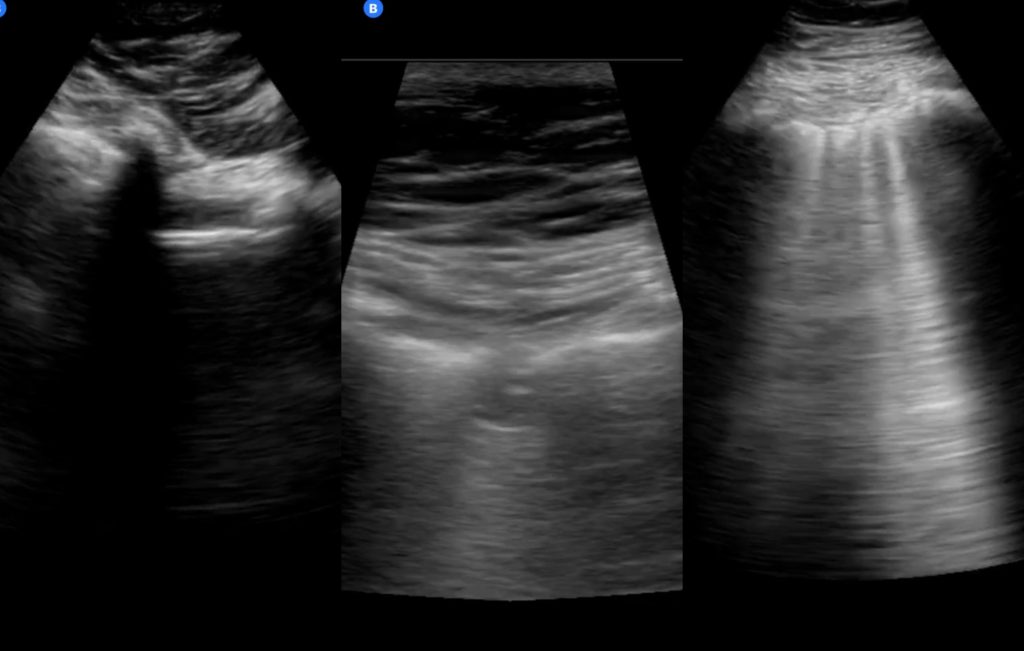

A new study published in the Canadian Medical Association Journal (CMAJ) examined ultrasound images taken from the lungs of a 64-year-old woman diagnosed with COVID-19, revealing how the virus can present itself in the lungs.

The ultrasound shows “pleural thickening, subpleural consolidation (also known as ‘skip lesion’) and multifocal B-lines,” researchers said.

The pleura are membranes that line the chest cavity and lungs, according to Mesothelioma.net, and they are typically thickened due to scarring, resulting in pleural thickening.

Consolidation occurs when your lungs are filled with something other than air, according to Healthline. It’s common with pneumonia and it often makes it difficult to breathe.

“These images show changes in the lung that occur due to the SARS-CoV-2 virus (which is responsible for COVID-19) infecting the lungs, and the body’s subsequent immune response to the infection,” said Dr. Anish Mitra, a critical care physician in Surrey, B.C.

“These ultrasound images indicate that there is inflammation in the lungs due to the infection.”

According to Mitra, ultrasound images such as these can help to guide treatment in patients with severe cases of COVID-19.

However, ultrasound should not be relied on during the diagnosis stage because inflammation — similar to what is shown in these images — can be seen in other viral pneumonias, including influenza.

“Rather, physicians can use lung ultrasound findings to help them make a diagnosis of COVID-19 or other diseases in the right clinical context,” Mitra said.

Credit: CMAJ. Credit: CMAJ